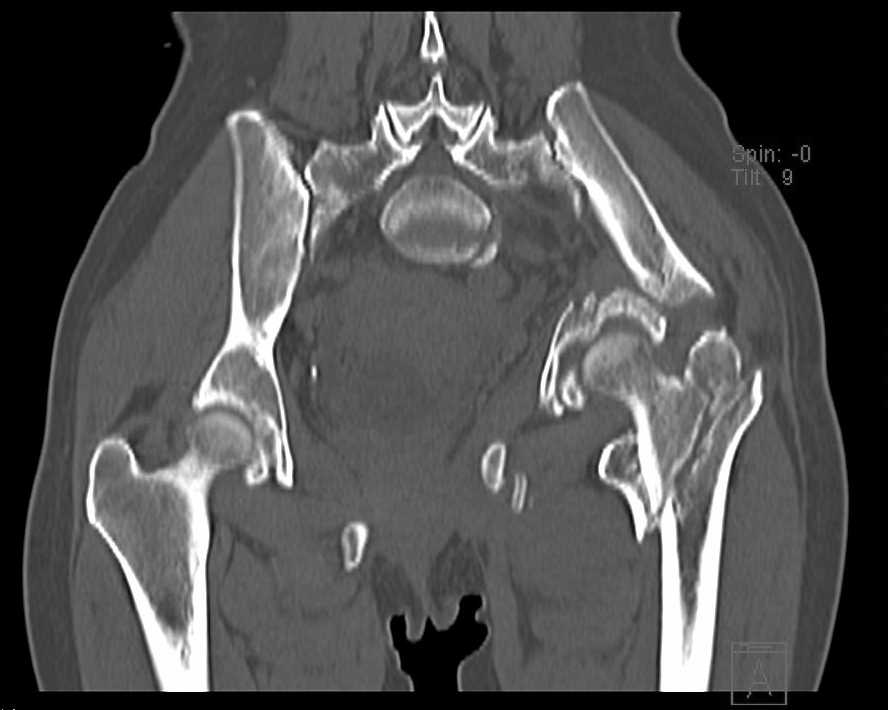

Больная 43 года (промышленный альпинист), 28.07.08 в результате падения с 5 этажа получила политравму:

Перелом свода и основания черепа. Вертикально-нестабильное повреждение таза, осложнённое разрывом мочевого пузыря. Чрезвертельный перелом левого бедра. Перелом правой таранной кости, переломовывих правой кубовидной кости. Тупая травма живота, разрыв печени, ушиб почек. Забрюшинная гематома. В день травмы - лапаротомия, ушивание ран печени. Разрыв мочевого пузыря не диагностирован. Течение болезни осложнилось развитием мочевого затёка и обширной пред- и забрюшинной флегмоны, сформировался свищ мочевого пузыря. 19.8.2008 вскрытие, дренировние флегмоны, ревизия мочевого пузыря, обтурация мочевого свища (свищ закрылся в октябре), 1.10.2008 некрэктомия, пластика по Шеде-Лидскому правой кубовидной кости. По результатам КТ диагностирован рак правой почки (диагностическая находка), 8.10.2008 нефрэктомия справа.

Имеется вертикальное смещение левой половины таза с выраженным отведением крыла (клинически подвижности нет), несросшийся низкий двухколонный перелом левой вертлужной впадины с потерей конгруэнтности, укорочение около5 см, застарелый разрыв лонного сочленения, неправильно сросшиеся переломы обеих ветвей правой лонной кости с укорочением, патологическая подвижность лоно-седалищного фрагмента слева. Правая нижняя конечность неопорна, несмотря на то, что лежа прямую ногу поднимает, ходит на левой ноге (ортопедическая обувь) с костылями, справа тазобедренный ортез. Седалищные нервы работают.Урологи отпустили больную на 6 мес.